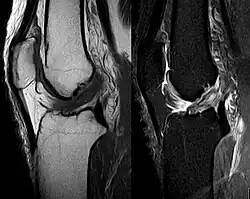

Aunque la exploración física llevada a cabo por un profesional experimentado puede ser diagnóstica, es habitual hacer una resonancia magnética de confirmación, que además proporciona imágenes de los tejidos blandos adyacentes, como los ligamentos o los cartílagos de la rodilla.[1] Además, permite valorar otras estructuras que pueden haber resultado dañadas, como los meniscos o los ligamentos colaterales. También se puede hacer una radiografía para evaluar si alguno de los huesos de la articulación de la rodilla se ha roto durante la lesión.[9]

Aunque la resonancia magnética es probablemente la prueba de imagen más utilizada para evaluar el estado del LCA, no siempre resulta la más fiable ya que la imagen puede estar distorsionada por el hematoma que se forma en la articulación tras la lesión.[29]